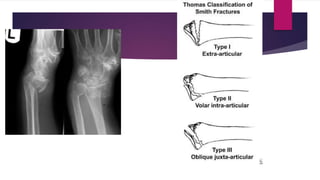

SMITH

 This fracture is a pronation injury, caused by a fall or blow on the back of the flexed wrist

 Reduction requires strong supination of the wrist but open reduction and internal fixation are

frequently necessary

 An above elbow cast is usually required during the 6 week period of immobilization to

maintain the position of supination

SMITH  This fractureis a pronation injury, caused by a fall or blow on the back of the flexed wrist  Reduction requires strong supination of the wrist but open reduction and internal fixation are frequently necessary  An above elbow cast is usually required during the 6 week period of immobilization to maintain the position of supination